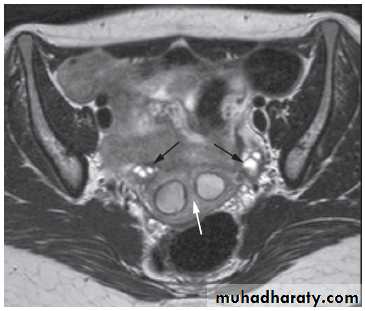

-The typical features of

polycystic ovaries on

ultrasound or MRI include

large volume ovaries

with multiple small

follicles arranged

around the periphery,

forming the appearance

of a ‘string of pearls’ .